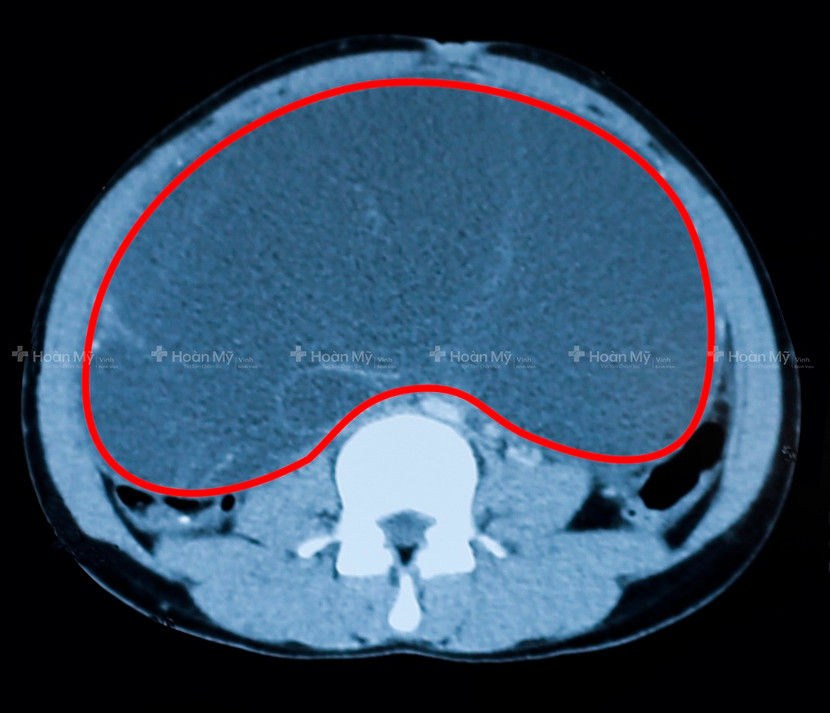

Hình ảnh siêu âm cho thấy khối u choán gần hết ổ bụng của bệnh nhân (ảnh bệnh viện cung cấp)

Tại bệnh viện Quốc tế Vinh, qua thăm khám lâm sàng kết hợp với kết quả siêu âm và chụp Cắt lớp vi tính bác sĩ chẩn đoán, H. bị u nang lớn týp 2 buồng trứng trái, KT 28 x 26 x 18cm, choán gần hết ổ bụng, chèn ép và đẩy lồi các quai ruột lên trên.